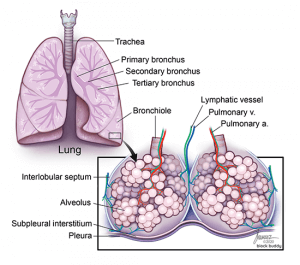

3. Anatomy

Secondary Pulmonary Lobule

- Located in the periphery of the lung.

- Comprised of 3 components: centrilobular, lobular parenchyma, and interlobular septa.

- Centrilobular: center portion of each lobule that is supplied by a respiratory bronchiole and pulmonary artery.

- These structures are surrounded by peribronchovascular interstitium.

- Lymph vessels run parallel to these structures.

- Lobular parenchyma: surrounds the centrilobular structures and contains the acini and intralobular interstitium.

- Acini: functional units of the lung that contains respiratory bronchioles, alveolar ducts, and alveoli.

- Intralobular interstitium: connective tissue around the alveoli that contains the pulmonary capillary bed.

- Interlobular septa: connective tissue that surrounds the lobular and centrilobular structures.

- Extend inward from subpleural interstitium and separate adjacent secondary pulmonary lobules.

- Contain pulmonary veins and lymph vessels.

- Interlobular septal thickening can occur from an increase in fluid within the septa (i.e. pulmonary edema).